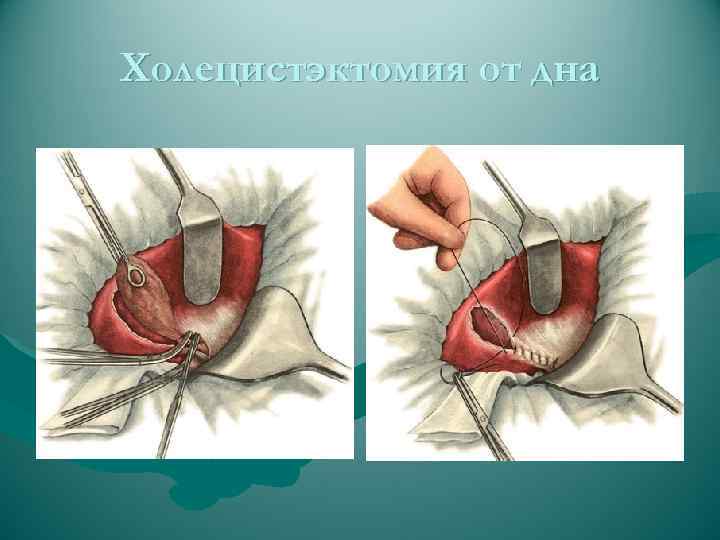

Холецистэктомия от дна

Холецистэктомия от дна

Холецистэктомия от дна

Холецистэктомия от дна